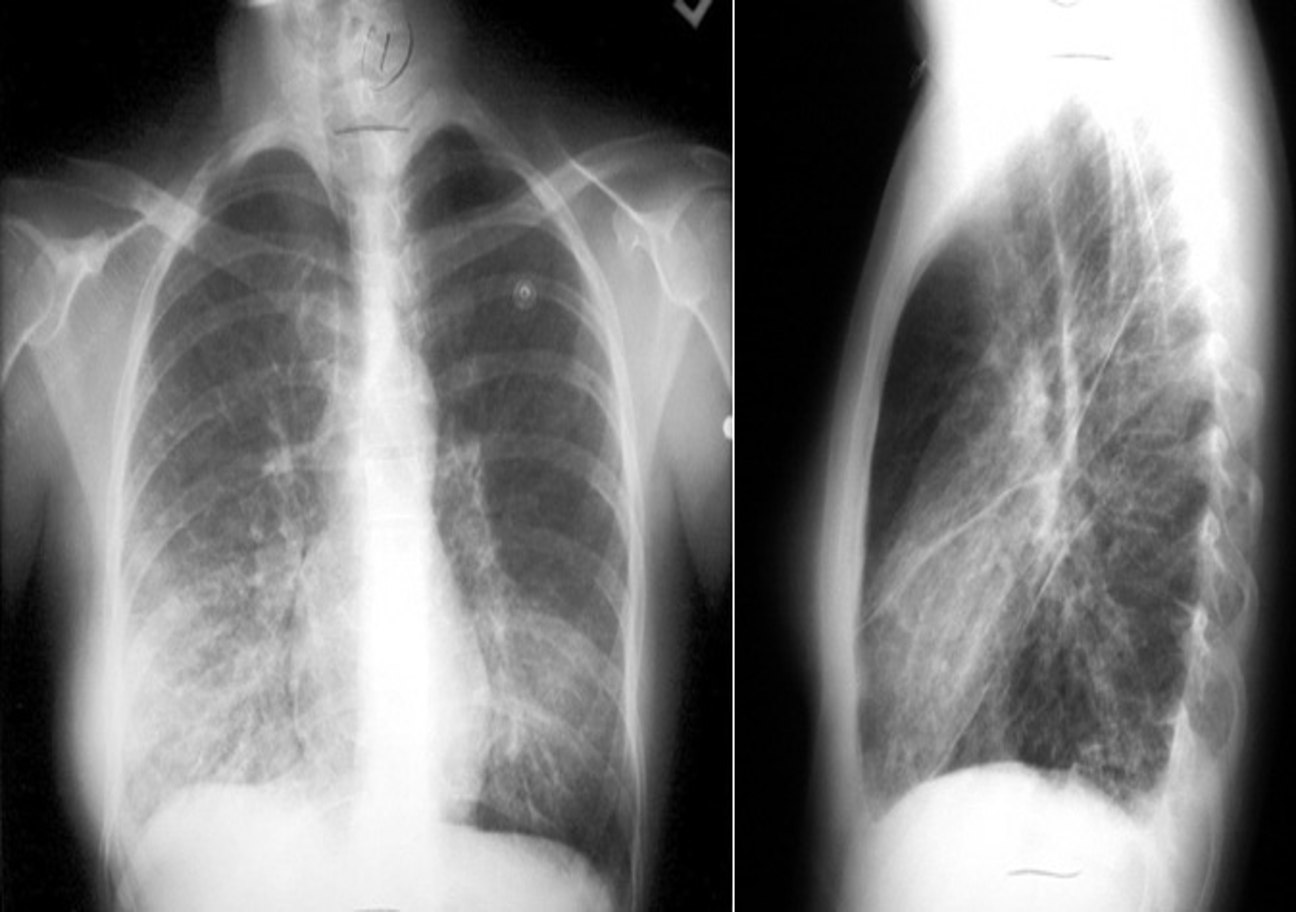

- Mycoplasma pneumonia: most commonly school age

- Patchy, segmental consolidation with hilar lymphadenopathy.

Image of chest x-ray displaying the interstitial pattern seen in viral pneumonia. The interstitial pattern shows fine lines radiating from the hila.

Anteroposterior radiograph from a child with a round pneumonia.

X-ray view of mycoplasma pneumonia

Imaging

RT. lower lobe; Lobar pneumonia: Opacity of one or more pulmonary lobes & Presence of air bronchograms

- Right lower lobe is most commonly affected by pneumonia

- Spine blackness increased reversibly (Spine sign); lower part opaque

Bronchopneumonia:

- Poorly defined patchy infiltrates scattered throughout the lungs.

- Presence of air bronchograms

Air Bronchogram

Normally, it is not possible to identify air in bronchi within normally aerated lung, because the walls of the normal bronchi are too thin and air-filled bronchi are surrounded by air in the alveoli. However, if the alveoli are filled with fluid, the air in the bronchi contrasts with the fluid in the adjacent lung.

CT chest (axial plane; lung window) of a patient with a history of bacterial pneumonia

Opacification of much of the right lower lobe parenchyma is the result of air space consolidation. Pulmonary vessels are obscured and patent airways

(air bronchograms, white dashed line) are seen.